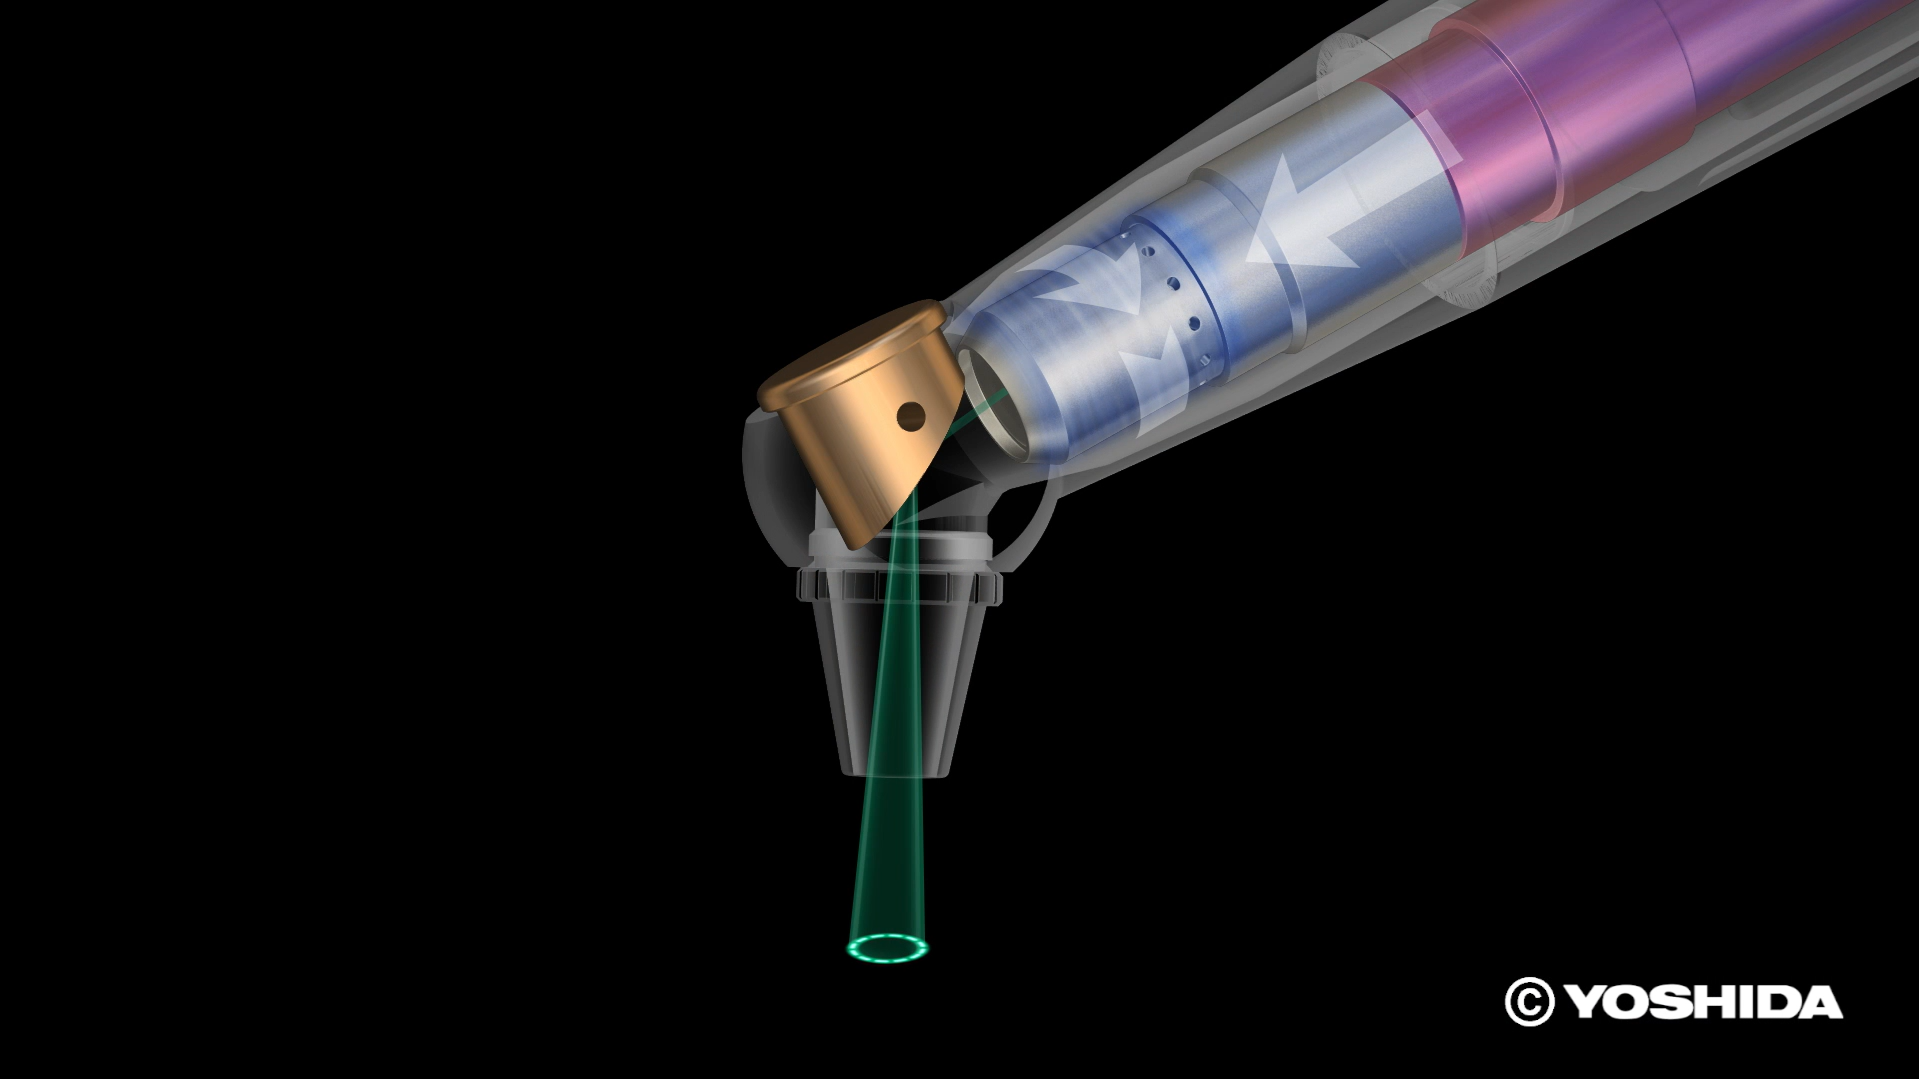

(1)オペレーザー商品とは、株式会社吉田製作所が製造する歯科用レーザー機器であって、「オペレーザー」を販売名に含む商品をいいます。